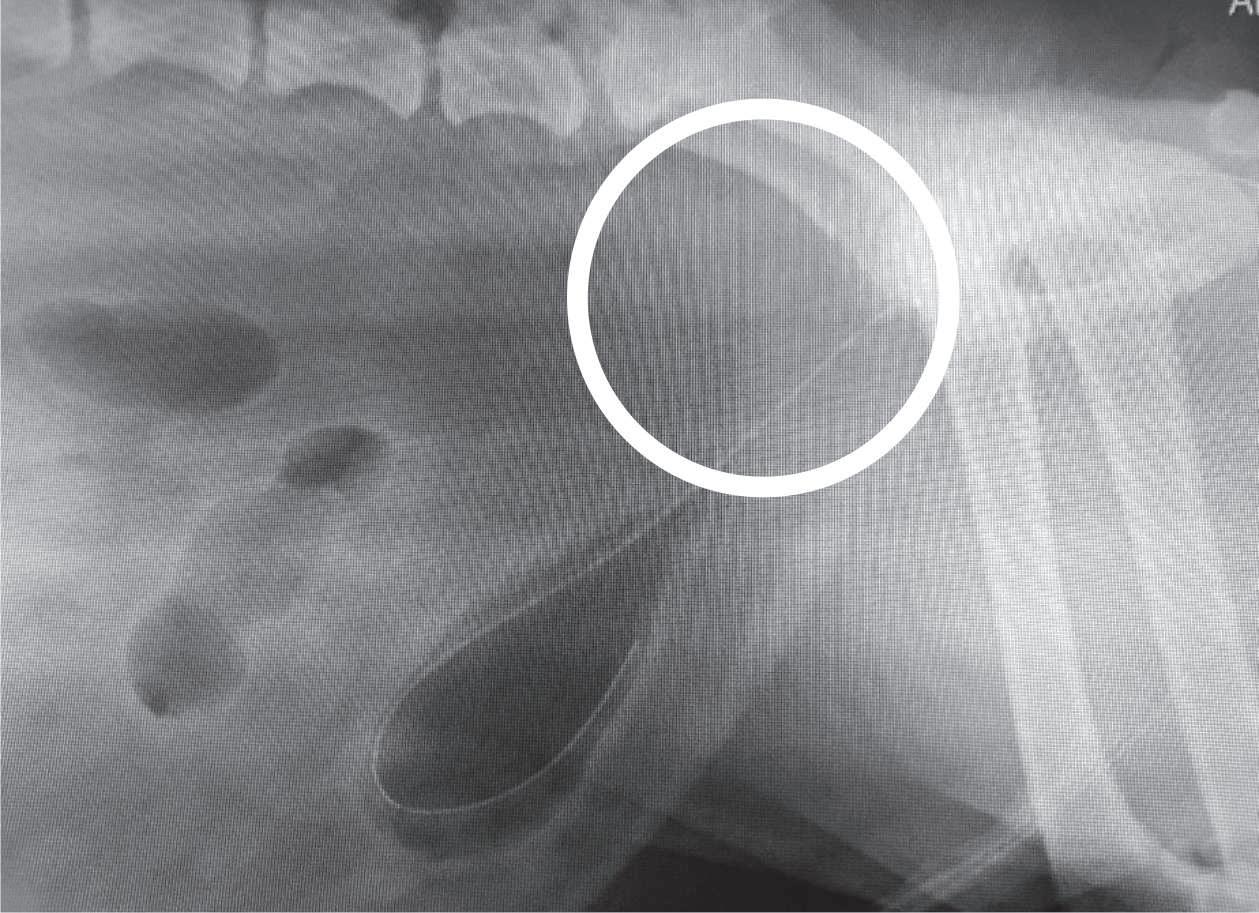

Quiste paraprostático.

Reporte de un caso clínico. . . . . . . . . . . . . . . . . . . . . . . . . . .40

Jorge Luna del Villar-Velasco, Norma Silvia Pérez-Gallardo, Ana Paula Sardina-Muñoz

Paraprostatic cyst. Report of a clinical case. . . . . . . . . . . . . . . . . . . . . . . . . . . . .40